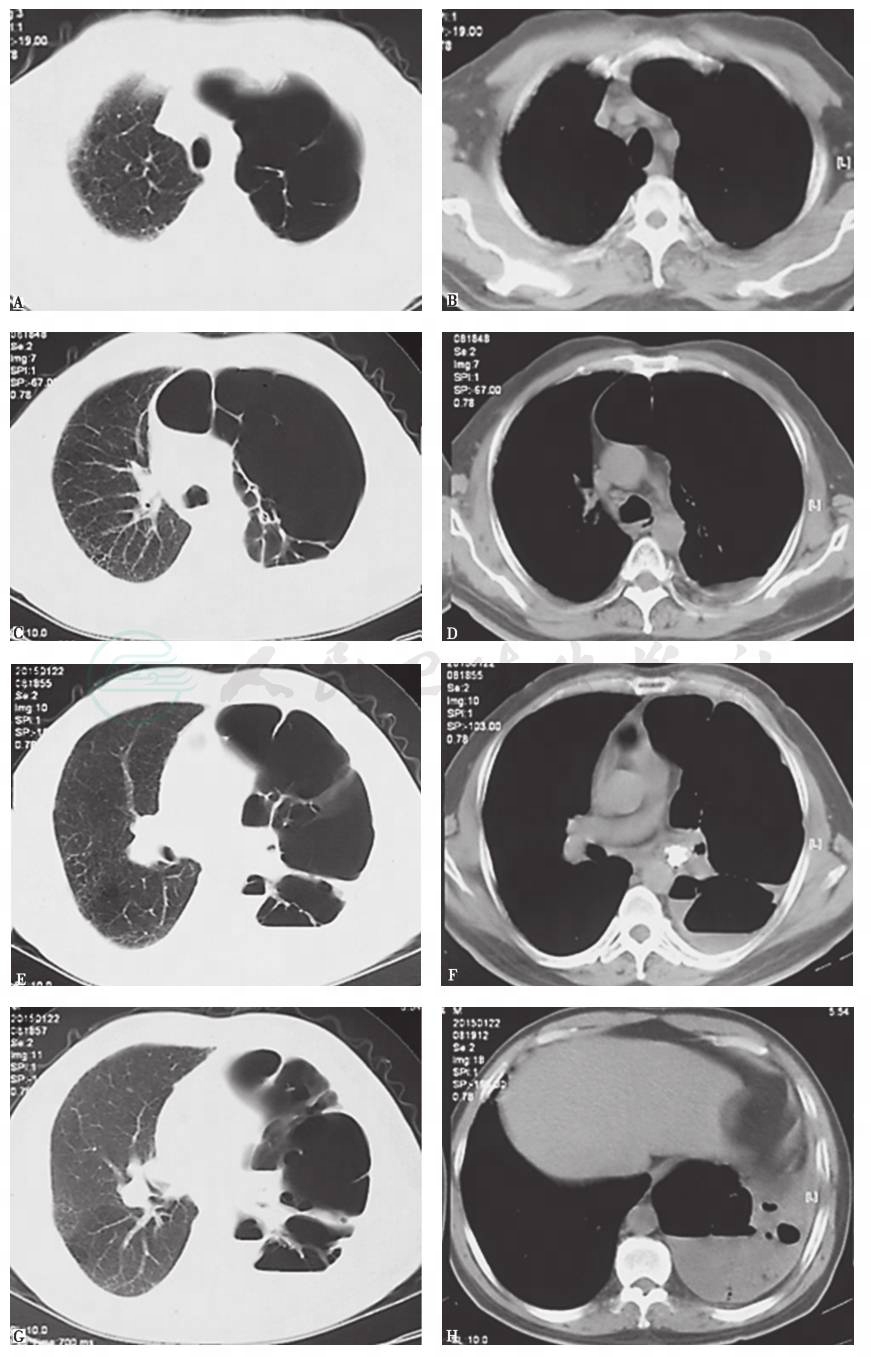

入院1个月前,胸部CT见左侧多发肺大疱,左下肺脓肿,其内见液平,左主支气管腔内高密度影,左侧少量胸腔积液(图1),抗感染治疗后未见好转(图2)。

图1 1个月前胸部CT表现

引自:主编:.呼吸系统疑难病例诊疗辨析.第1版.ISBN:978-7-117-26415-0